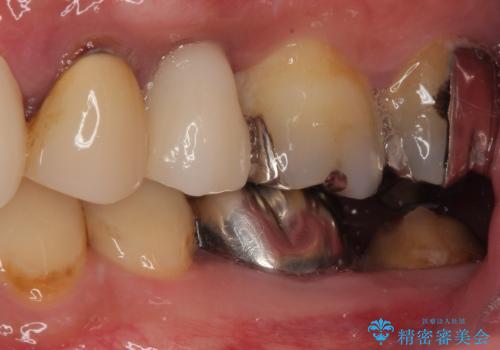

抜歯即時インプラント後、治癒期間を経て、約3か月でセラミックによる最終補綴が完了しました。